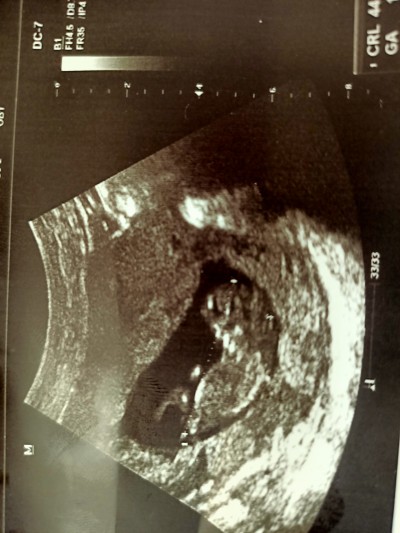

Kızlar 11+6 sizce kız mı erkek mi tahmin edebilen var mı ❤️

Kiz pipi felan gormiyorm daha küçük galiba  bilememki post yukari ciksn belki bilen olr

Kız gibi duruyor belli mi

nedense erkek diyesim geldi. benim bebeğin de 12 haftalık fotosu var bundan farklı yani benim ki kıza benziyor demişti. ona dayanarak söylüyorm:) bende bunu erkeğe benzettim tabi öncelik sağlıklı olsun inşallah

Içimden erkek geçti

Kız gibi canım